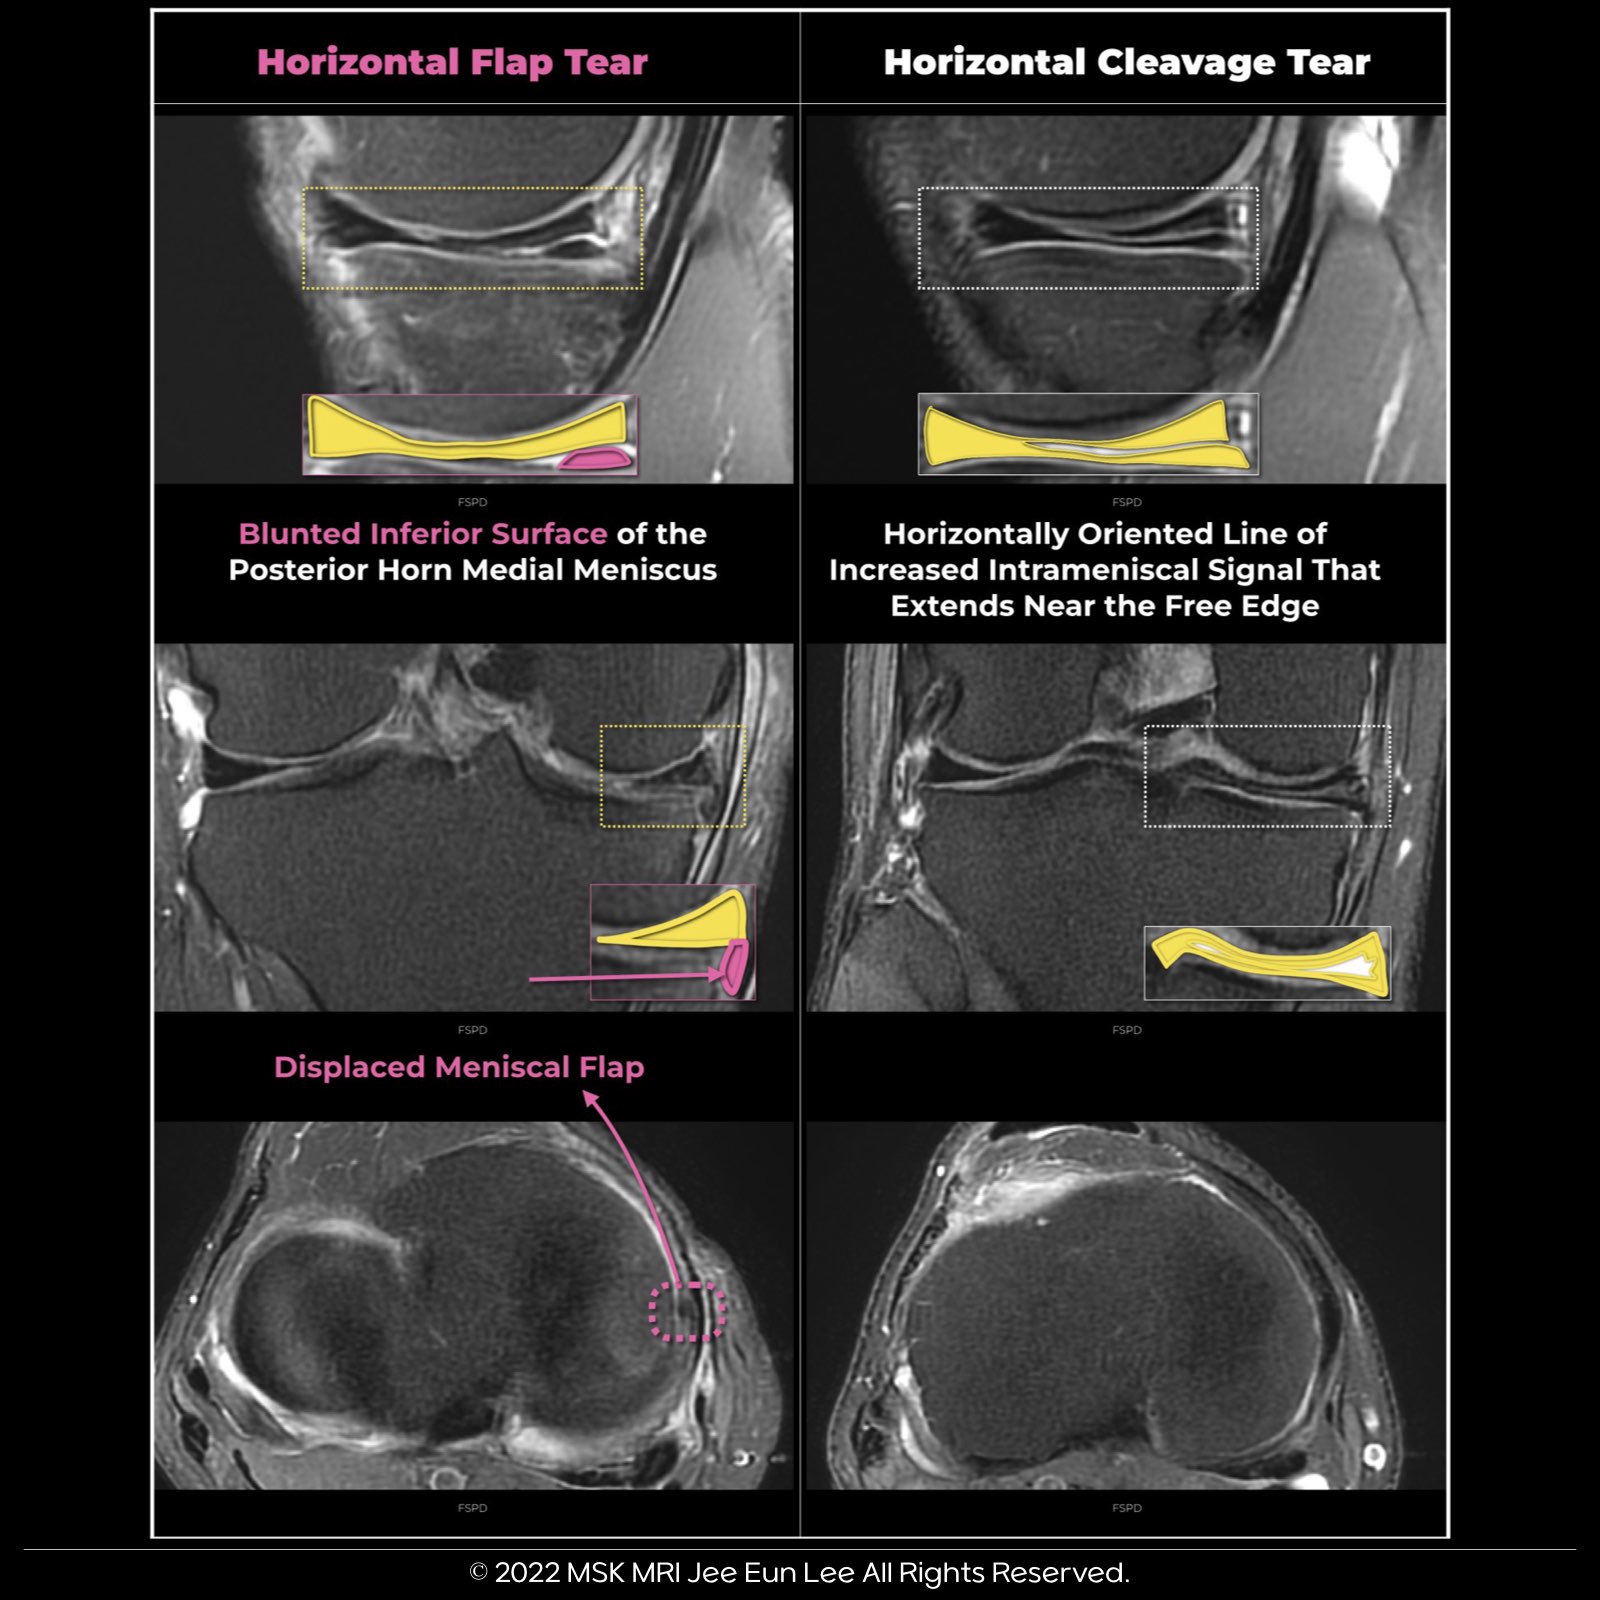

Horizontal Flap Tear

- In a horizontal flap tear, we observe a meniscal fragment displaced deeper than the Medial Collateral Ligament (MCL). However, in a horizontal cleavage tear, there is no meniscal fragment situated deeper than the MCL.

- ๐๏ธ๐จ๏ธ Diagnosing a horizontal flap tear can be challenging and is sometimes overlooked. Given that most displaced meniscal tears are found medially and posterolaterally in the medial meniscus, it's crucial to scrutinize these areas closely.

Horizontal Cleavage Tear

- Horizontal meniscal tears occur within the meniscus in a horizontal plane, dissecting through its circumferential collagen fibers.

- They appear as horizontally oriented lines with increased intrameniscal signal, often extending to either the superior or inferior surface of the meniscus, typically near the free edge.

- Most horizontal tears reach the meniscus's inferior surface.

- ๐ When a horizontal tear extends to the meniscal apex, it's referred to as a pure horizontal cleavage tear.